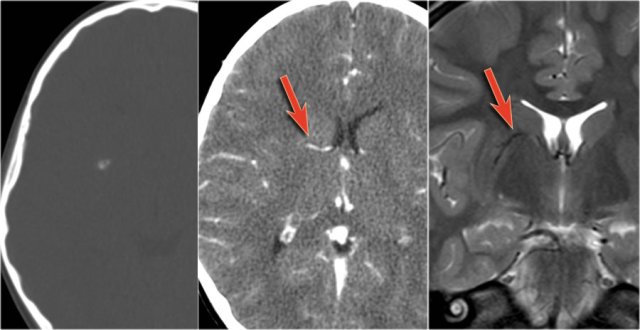

The images show mesial temporal sclerosis with a hyperintense and shrunken hippocampus (red arrows), and secondary enlargement of the left temporal horn of the left laterale ventricle.

Also notice associated subcortical hyperintensity in the left temporal lobe indicating focal cortical dysplasia.

35-year-old patient with refractory temporal lobe epilepsy.